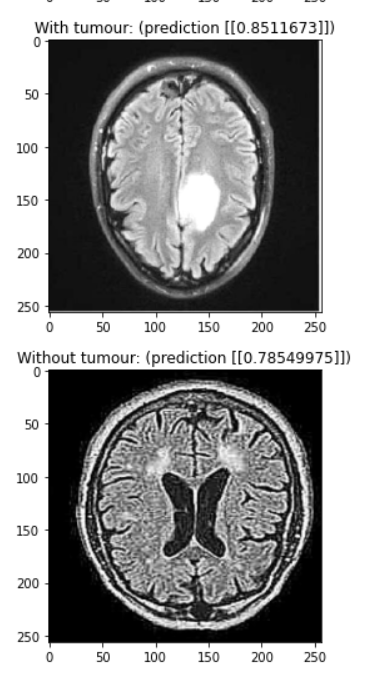

Our model is a convolutional neural network designed to detect brain tumours in MRI scans. You need a trained doctor to conclusively find a brain tumour, but our model can rule out scans that definitely don’t have a tumour and flag potential tumours for evaluation by a human doctor.

We used a combination of batch normalization and dropout to reduce overfitting, allowing us to train for over 80 epochs before noticing any overfitting. The main feature detection layers consist of convolutional layers with batch normalization where every second or third layer has a stride of (2, 2) to downsample the image. Each of these convolutional layers uses the ReLU activation function. We added a dropout of 0.2 in between the final convolutional layer and the output layer to reduce overfitting. We added this while struggling with a problem with our data, so it would be interesting to try removing this layer to see if it’s really necessary. Finally, our output layer is a single dense neuron with a sigmoid activation function. It would be interesting to experiment with using logits instead of a probability output.

Despite our different time zones, we were able to get together to work and accomplish the tasks. Utilizing different skill sets, we were also able to create a high-standard slide presentation and present with the passion that we have for the project. Additionally, after running into some issues, we were able to achieve a diagnostic accuracy of 90% in the time that we had.